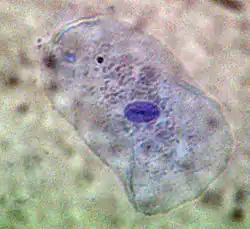

Cavitatea bucală (lat. bucca = obraz), gura, orificiul oral sau orificiul bucal, este segmentul inițial, cranial, al tubului digestiv la mamifere și om. Fiind o deschidere a corpului care este delimitată lateral de obraji, superior de palat, inferior de planșeul bucal.